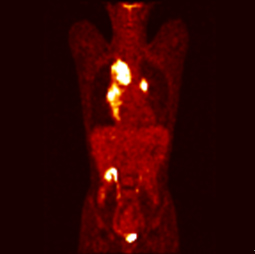

림프종 양전자방출 단층촬영